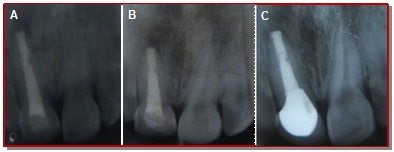

In the present study, the ability of mineral trioxide aggregate in the formation of apical plug for healing of large periapical lesion with open apex was assessed and evaluated the clinical outcome. Fifteen participants with periapical lesion at the upper anterior teeth with open apex were treated with mineral trioxide aggregate. The effect on healing of apical size was evaluated at 3, 6, and 12 months by radiological examinations in the form of periapical index criteria, diameter of the lesion size and the presence or absence of apical tissue barrier. The results found that neither pain nor any sinus was detected at 12 months. The mean size of the apical lesion was gradually reduced from 5.1 × 3.8 to 1.5 × 0.9 mm and mean PAI was reduced from 3.3 to 1.7 mm. The differences between mean size of periapical lesion at preoperative and 12 months observation period was also statistically significant (p<0.05). The clinical success shown significant success rate of 93.3% analyzed with Z-test. In conclusion, tooth with open apex can be successfully treated with mineral trioxide aggregate apexification technique followed by root canal obturation.